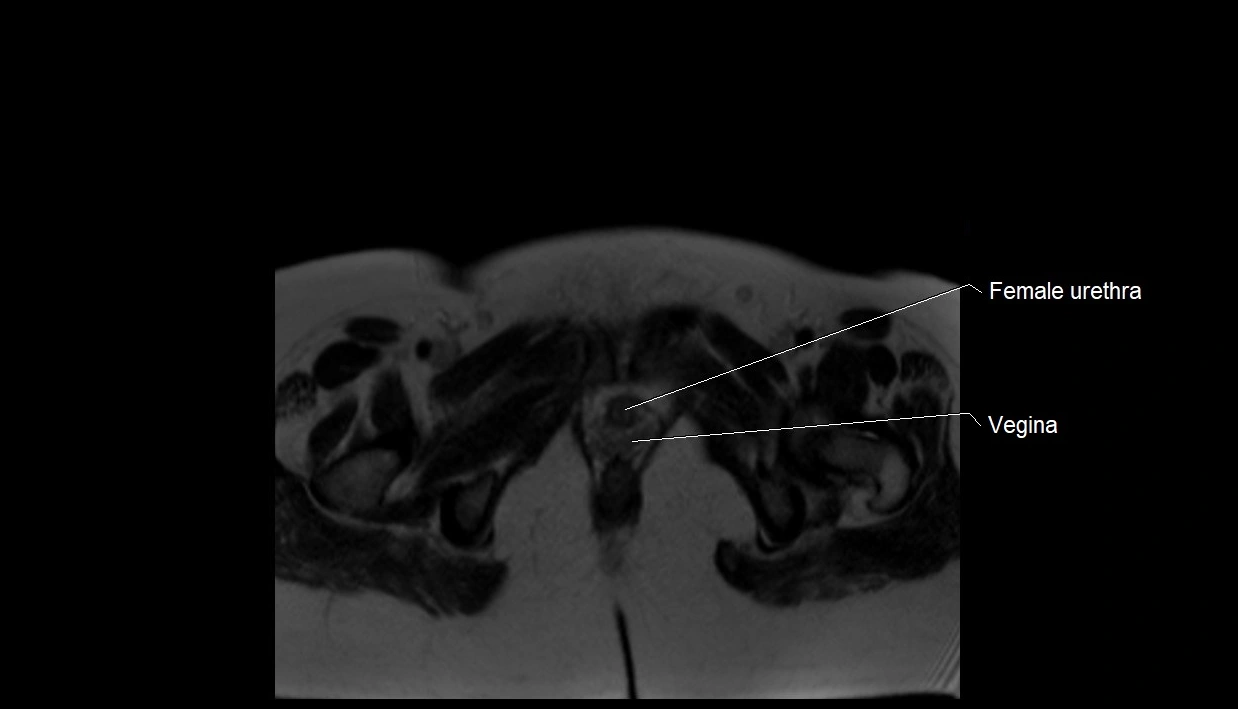

MRI Appearance

T2 HASTE (T2 GRE):

• Amniotic fluid shows very bright hyperintense signal

• Provides natural contrast against fetus and placenta

• Small particles (vernix) may appear as scattered hypointense foci within bright fluid

T1 GRE:

• Amniotic fluid shows low signal intensity (dark)

• Hemorrhage, infection, or proteinaceous content may cause focal or diffuse high signal intensity

MRI image

image